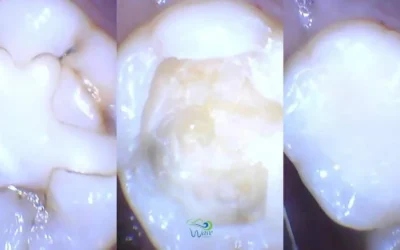

What Is SDF? Can It Stop Cavities In Children?

What Is SDF? Can It Stop Cavities In Children? While Silver Diamine Fluoride has some limitations,...